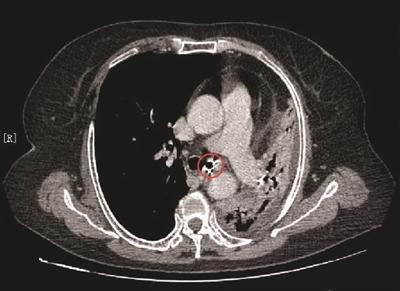

CT片上的金属影原来是颗假牙。

带着疑问,医生多次询问李阿姨,然而她一口咬定没做过肺部手术,也从没有误吞过异物。为了谨慎起见,医院组织放射科、呼吸科等多学科专家联合会诊,专家一致认为,患者左支气管内有1.5厘米的金属影,异物滑落的可能性很大。

随后,呼吸科朱际平副主任医师为患者实施支气管镜下气管异物取出术。从电子支气管镜中,清楚地看到左支气管入口被一团黄色异物堵得严严实实,从异物中伸出的两个金属钩将其挂在气管壁上。